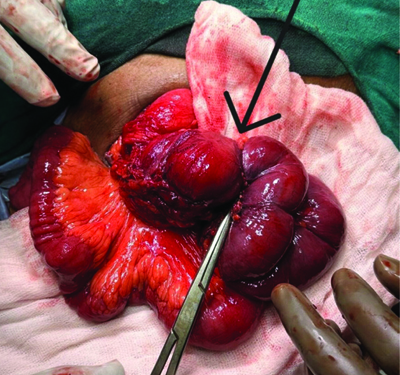

The patient was planned for exploratory laparotomy with ileocolic anastomosis. Intraoperative findings showed a normal omentum, but a thickened and fibrotic stricture mass was palpated at the ileocolic junction, encompassing the terminal ileum, cecum and a portion of the ascending colon. The mass was adherent to the retroperitoneum and positioned over the abdominal aorta. Tissue suspected to be adherent to the aorta was sent for histopathological analysis, which was indicative of a potential infective etiology. Based on the surgeons’ intraoperative expertise and clinical diagnosis, the ileoileal mass was resected with sufficient margins, followed by ileocolic anastomosis [Table/Fig-2,3].

Intraoperative picture showing ileoileal stricture.